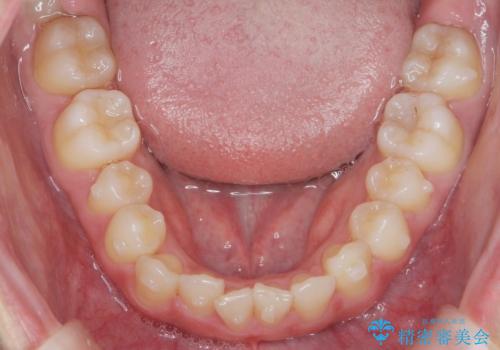

マウスピース矯正で前歯のガタつきを改善

- 上下の前歯のガタつきの改善を求めて、矯正治療を希望され来院されました。

矯正検査の結果、マウスピース矯正システム インビザラインの適応であることからワイヤーを用いず矯正治療を進めることとしました。

1日20時間以上の使用時間をきっちりと守っていただけたため、良好な治療結果、歯並びを手に入れることができました。